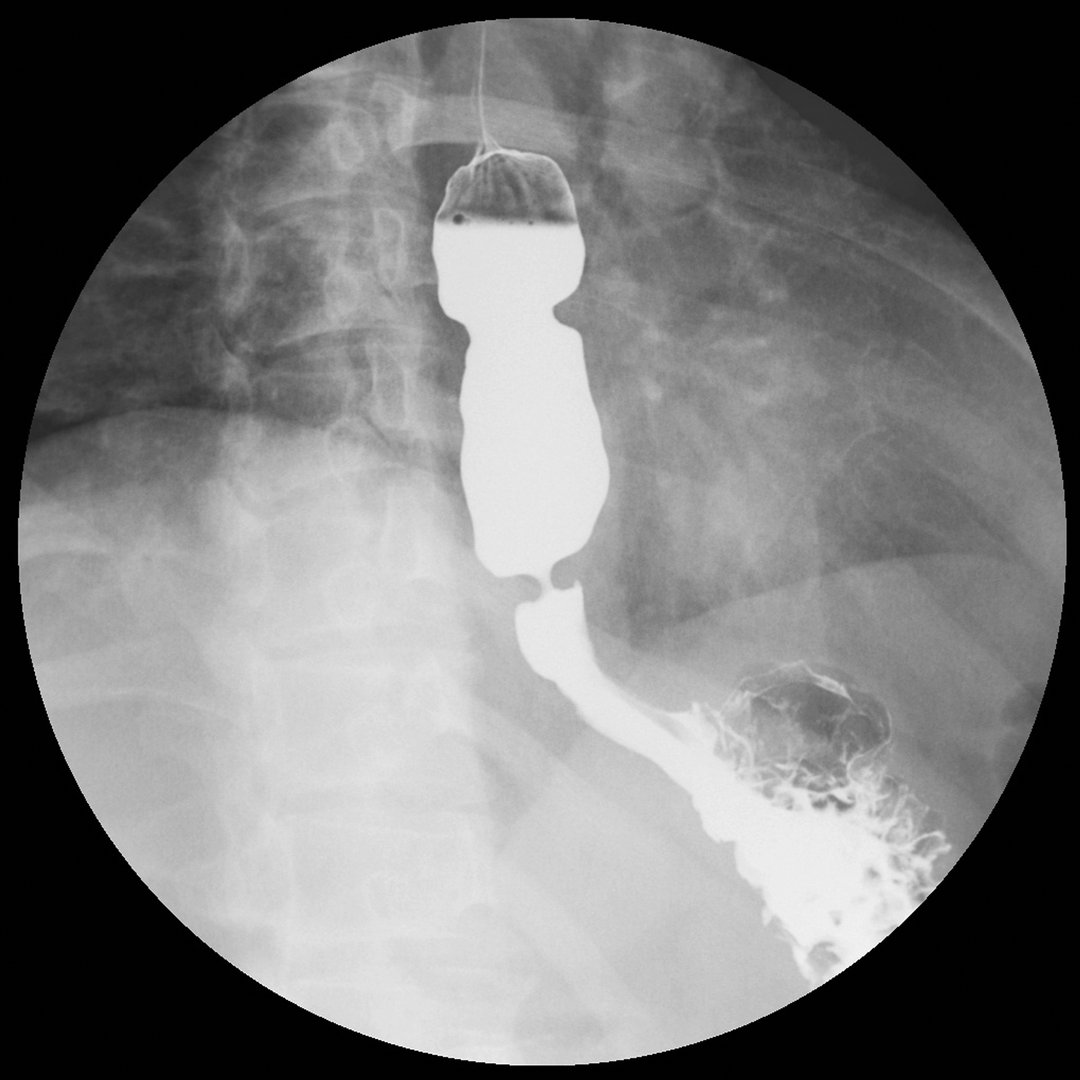

Enfermedad por Reflujo

Diagnóstico y tratamiento especializado del reflujo gastroesofágico en niños y bebés